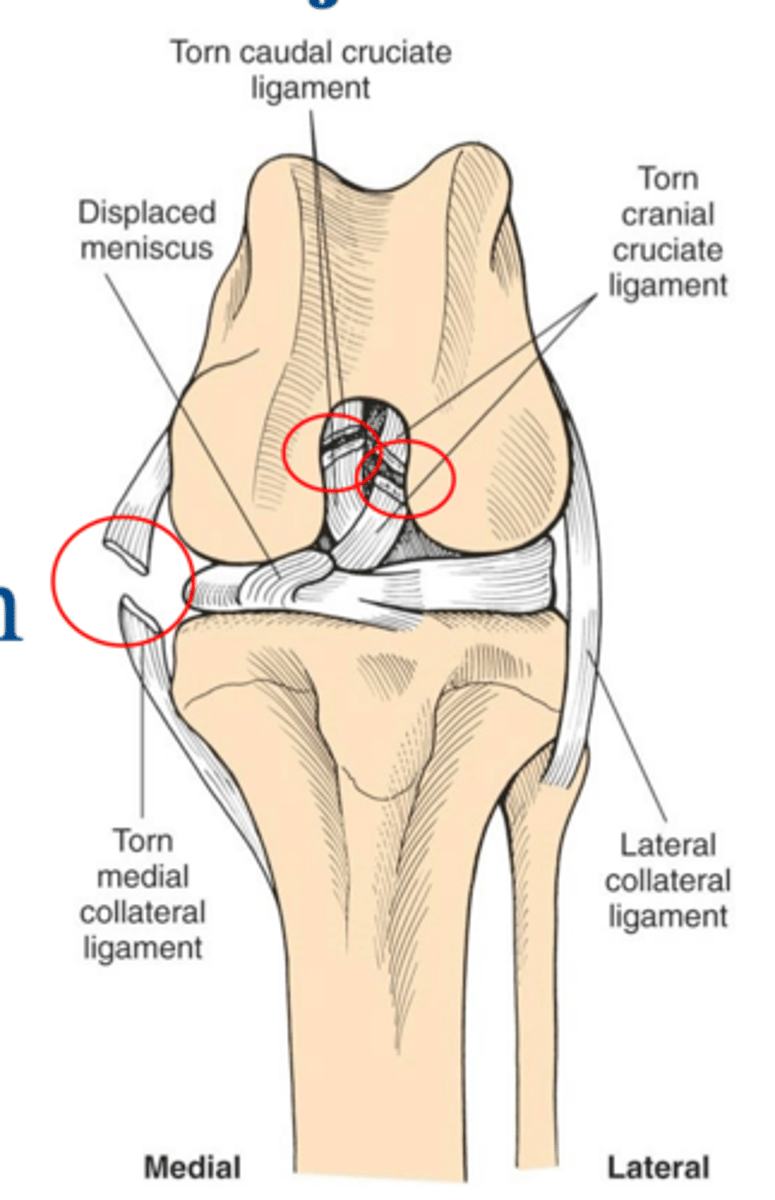

in terms of surgical anatomy of the stifle following damage due to trauma...

loss of cranial and caudal cruciate lig. and disruption of medial restraints

what damage is notable in this deranged stifle joint

1. cranial and caudal cruciate ligament tears

2. failure of primary and secondary medial restraints

3. peripheral medial meniscal tears

what is the common triad of multiple ligament injuries

deranged stifle...multiple lig. injuries often associated w/ meniscal injury and stifle luxation

what condition is shown here